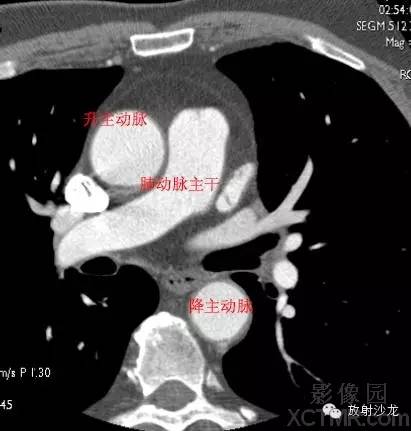

A.Aorta-Ascending Aorta升主动脉

D. Aorta-Descending Aorta降主动脉

PA -Pulmonary Artery肺动脉